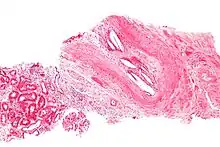

| Micrograph showing a cholesterol embolus in a medium sized artery of the kidney. Kidney biopsy. H&E stain. | |

The microscopic examination of tissue (histology) gives the definitive diagnosis. The diagnostic histopathologic finding is intravascular cholesterol crystals, which are seen as cholesterol clefts in routinely processed tissue (embedded in paraffin wax).[7] The cholesterol crystals may be associated with macrophages, including giant cells, and eosinophils.

The sensitivity of small core biopsies is modest, due to sampling error, as the process is often patchy. Affected organs show the characteristic histologic changes in 50-75% of the clinically diagnosed cases.[3][5] Non-specific tissue findings suggestive of a cholesterol embolization include ischemic changes, necrosis and unstable-appearing complex atherosclerotic plaques (that are cholesterol-laden and have a thin fibrous cap). While biopsy findings may not be diagnostic, they have significant value, as they help exclude alternate diagnoses, e.g. vasculitis, that often cannot be made confidently based on clinical criteria.